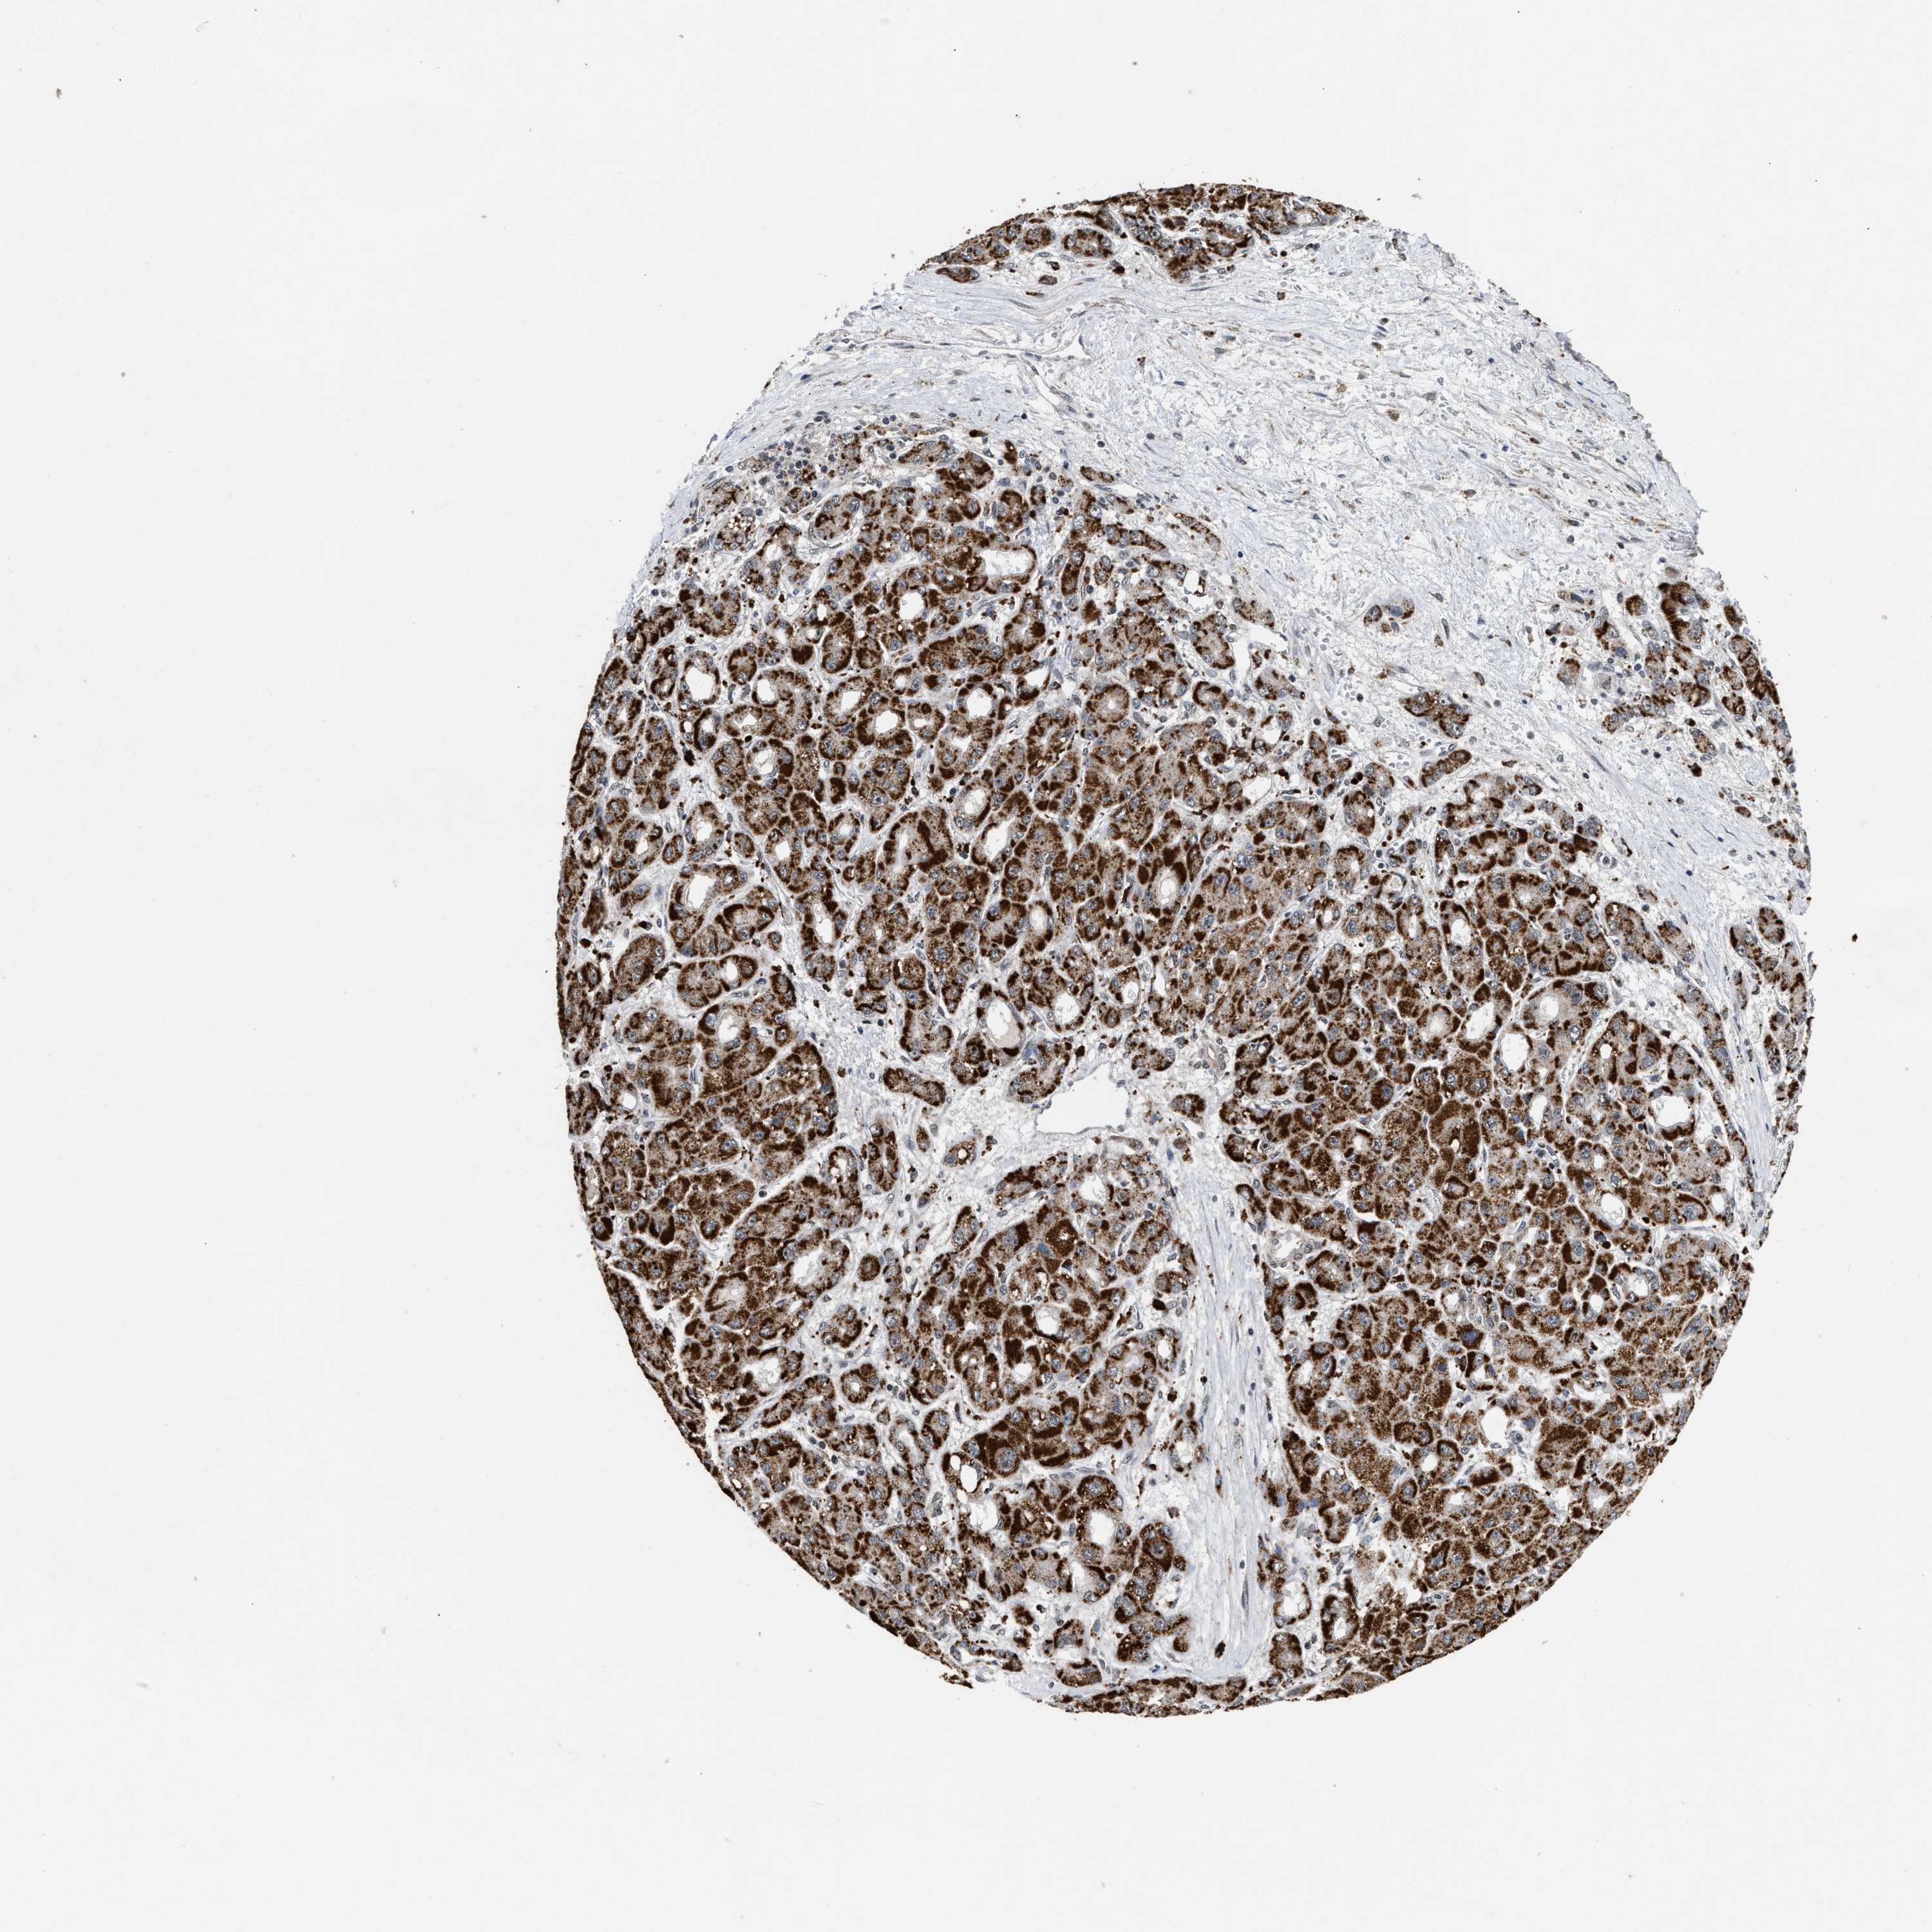

LIVER CANCER - Protein expressioni

A mouse-over function shows sample information and annotation data. Click on an image to view it in a full screen mode. Samples can be filtered based on level of antibody staining by selecting one or several of the following categories: high, medium, low and not detected. The assay and annotation is described here.

Note that samples used for immunohistochemistry by the Human Protein Atlas do not correspond to samples in the TCGA dataset.

Antibody stainingi

Antibody staining in the annotated cell types in the current human tissue is reported as not detected, low, medium, or high, based on conventional immunohistochemistry profiling in selected tissues. This score is based on the combination of the staining intensity and fraction of stained cells.

Each image is clickable and will lead to virtual microscopy that enables deeper exploration of all samples and also displays staining intensity scores, fraction scores and subcellular localization as well as patient and tissue information for each sample.

Antibody HPA021192

Antibody HPA021195

Antibody HPA028759

Antibody CAB021094

Staining

High

Medium

Low

Not detected

Location

Nuclear

Cytoplasmic/membranous

Cytoplasmic/membranous,nuclear

Cholangiocarcinoma

Carcinoma, Hepatocellular, NOS